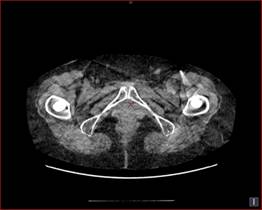

逐次近似法を用いたノイズ低減処理(GE製の場合はASiR:Adaptive Statistical Iterative Reconstructionという名称)とは、システム統計モデルに加えて、解剖学的構造も考慮した、新しい画像再構成法です。この手法は、空間分解能に影響を与えることなく、画像ノイズを削減する画像再構成アルゴリズムで、画質の向上、被ばくの低減を実現できます。